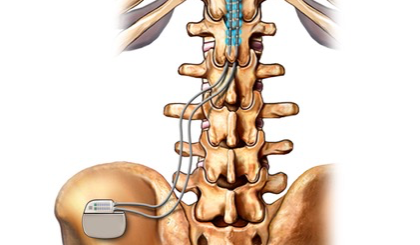

- Neuromodulazione